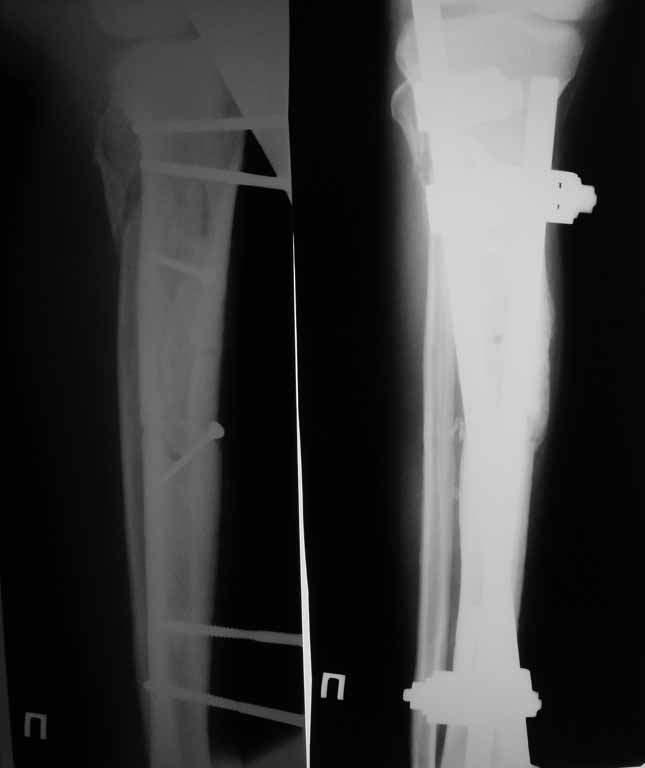

Привожу пример: Пациент с открытой тяжелой ЧМТ.

Диагноз при поступлении: Открытый оскольчатый перелом свода и основания черепа,субдуральная гематома, ушиб головного мозга тяжелой степени. Открытый оскольчатый перелом костей правой голени. Шок 3 Кома 3

При поступлении оперирован : трепанация, ПХО, остеосинтез голени.

Консолидация в аппарате внешней фиксации к 2 месяцам. Аппарат снят через 2,5 месяца.